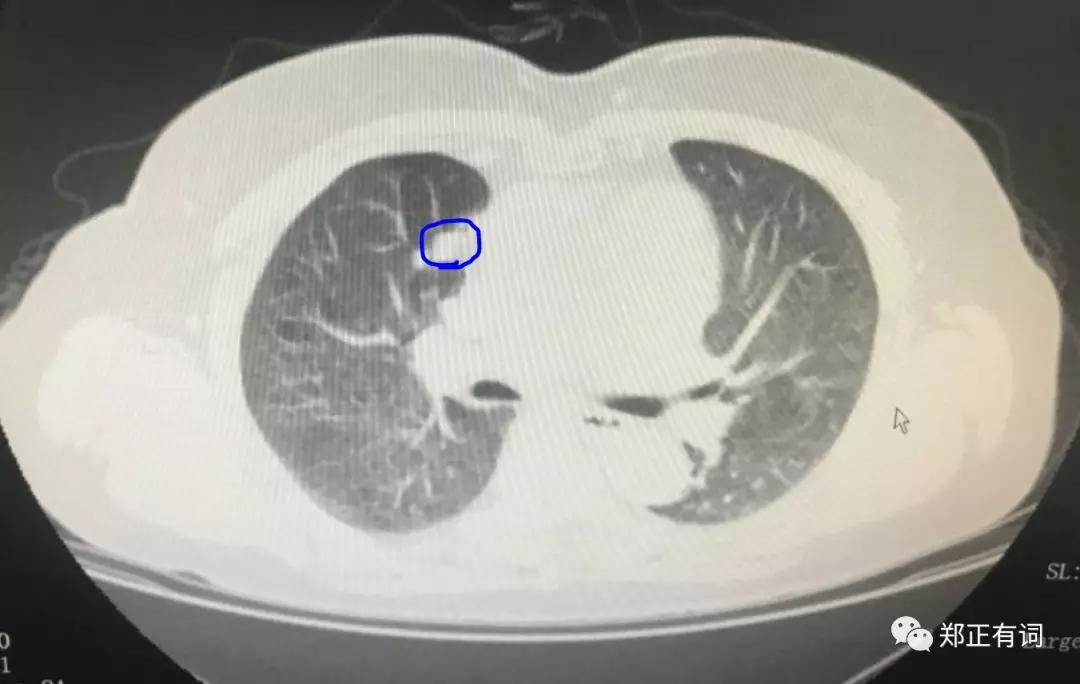

这是一个海南籍的病友,听说广医肿瘤看肺癌不错,就经由熟人介绍过来求诊。入院以后完善CT检查,发现这个病人右上肺近纵隔面存在一个最大径约16mm的实性结节;

而与此同时,右上肺尖段还有一个混合实性结节,疑似恶性。